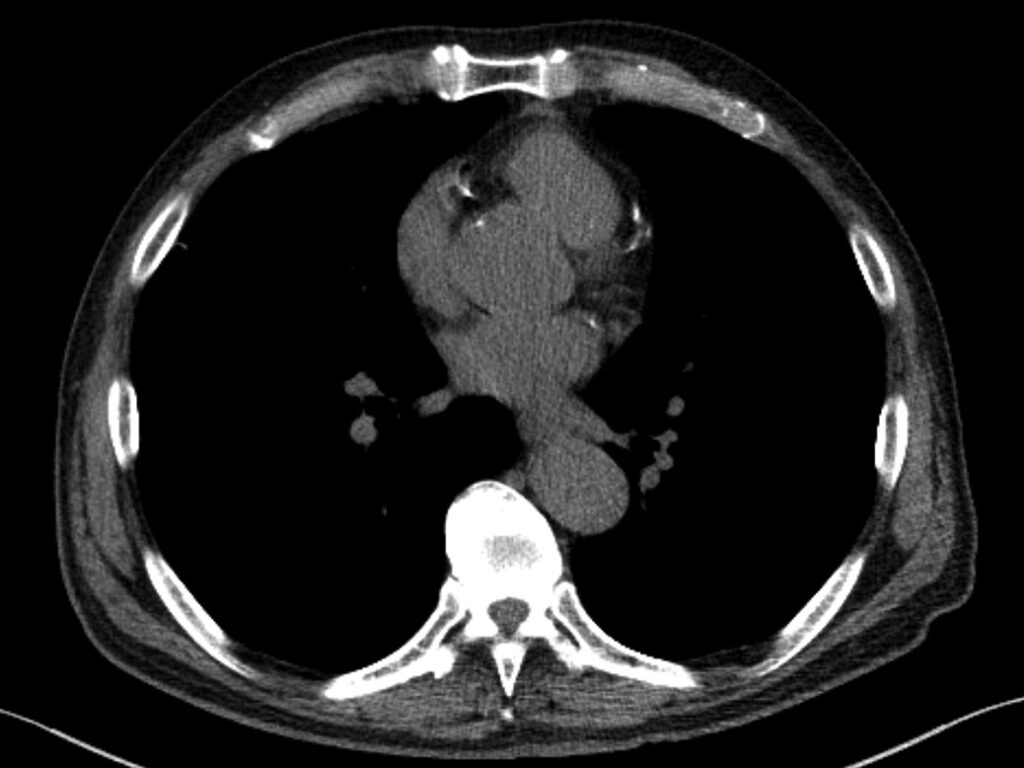

AMA also tabled a resolution regarding expanded promotion and usage of low-dose CT (LDCT) to screen both lung cancer and coronary artery disease via coronary calcium scoring. Emphasizing the modality’s value as a public health tool for high-risk individuals, particularly those with pack-year history of smoking, LDCT delivers far less radiation than standard CT and can detect small lung nodules early. Indeed, crucial research from the National Lung Screening Trial shows it can reduce lung cancer mortality by up to 20% [5].

And yet, uptake is still cripplingly low; fewer than 6% of eligible patients receive LDCT screening. To buttress the resolution’s goals, the American College of Radiology is launching complementary efforts, including expanding its early lung cancer registry to capture incidental findings from routine CTs, not just formal screening exams [6]. Such distinction will deepen insights into nodule detection and follow-up.

Fig. 2—73-year-old patient who underwent lung cancer screening by LDCT of the chest. Axial CT image shows coronary artery calcification (CAC). CAC was assessed as severe by consensus visual analysis.

More broadly, many hospitals have begun offering low- or no-cost LDCT screenings as an entry point for preventive care. Apropos, this resolution specifically solicits a coordinated national effort of public awareness campaigns and provider education to ensure affordable, widespread access to this potentially life-saving tool.